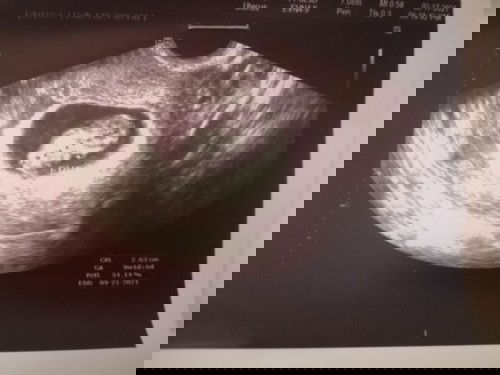

No gestational sac. Only thickened endometrium lang ang nakita at 1st ultrasound. 5 weeks ako nun based on my LMP. pinabalik ako ng ob ko sa 10th week ko. At nakita na sya wakas. 9 weeks and 1 day pa sya. Sa mga 1st time nagbuntis jan at same yung story sa akin. dont worry. Pray lang always kasi magpapakita talaga yan sya. #firstbaby #1stimemom